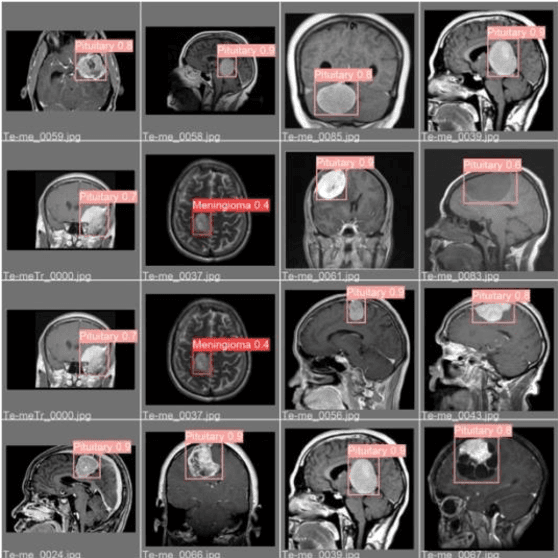

Abstract:An expansion of aberrant brain cells is referred to as a brain tumor. The brain's architecture is extremely intricate, with several regions controlling various nervous system processes. Any portion of the brain or skull can develop a brain tumor, including the brain's protective coating, the base of the skull, the brainstem, the sinuses, the nasal cavity, and many other places. Over the past ten years, numerous developments in the field of computer-aided brain tumor diagnosis have been made. Recently, instance segmentation has attracted a lot of interest in numerous computer vision applications. It seeks to assign various IDs to various scene objects, even if they are members of the same class. Typically, a two-stage pipeline is used to perform instance segmentation. This study shows brain cancer segmentation using YOLOv5. Yolo takes dataset as picture format and corresponding text file. You Only Look Once (YOLO) is a viral and widely used algorithm. YOLO is famous for its object recognition properties. You Only Look Once (YOLO) is a popular algorithm that has gone viral. YOLO is well known for its ability to identify objects. YOLO V2, V3, V4, and V5 are some of the YOLO latest versions that experts have published in recent years. Early brain tumor detection is one of the most important jobs that neurologists and radiologists have. However, it can be difficult and error-prone to manually identify and segment brain tumors from Magnetic Resonance Imaging (MRI) data. For making an early diagnosis of the condition, an automated brain tumor detection system is necessary. The model of the research paper has three classes. They are respectively Meningioma, Pituitary, Glioma. The results show that, our model achieves competitive accuracy, in terms of runtime usage of M2 10 core GPU.